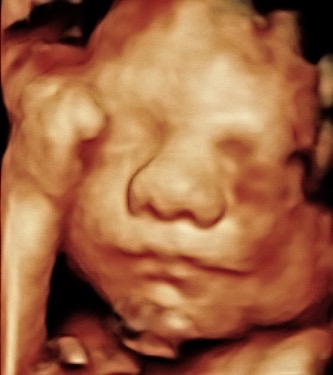

Hi, my name is Crystal Heller, and I’m the owner of Miracle 3D Moments. For the past five years, I’ve had the privilege of helping moms, dads, and families see and bond with their babies before they’re born. It’s been the most rewarding part of my life watching the smiles, the tears of joy, and the comfort that comes when a mom-to-be sees her little one moving, yawning, and even smiling.